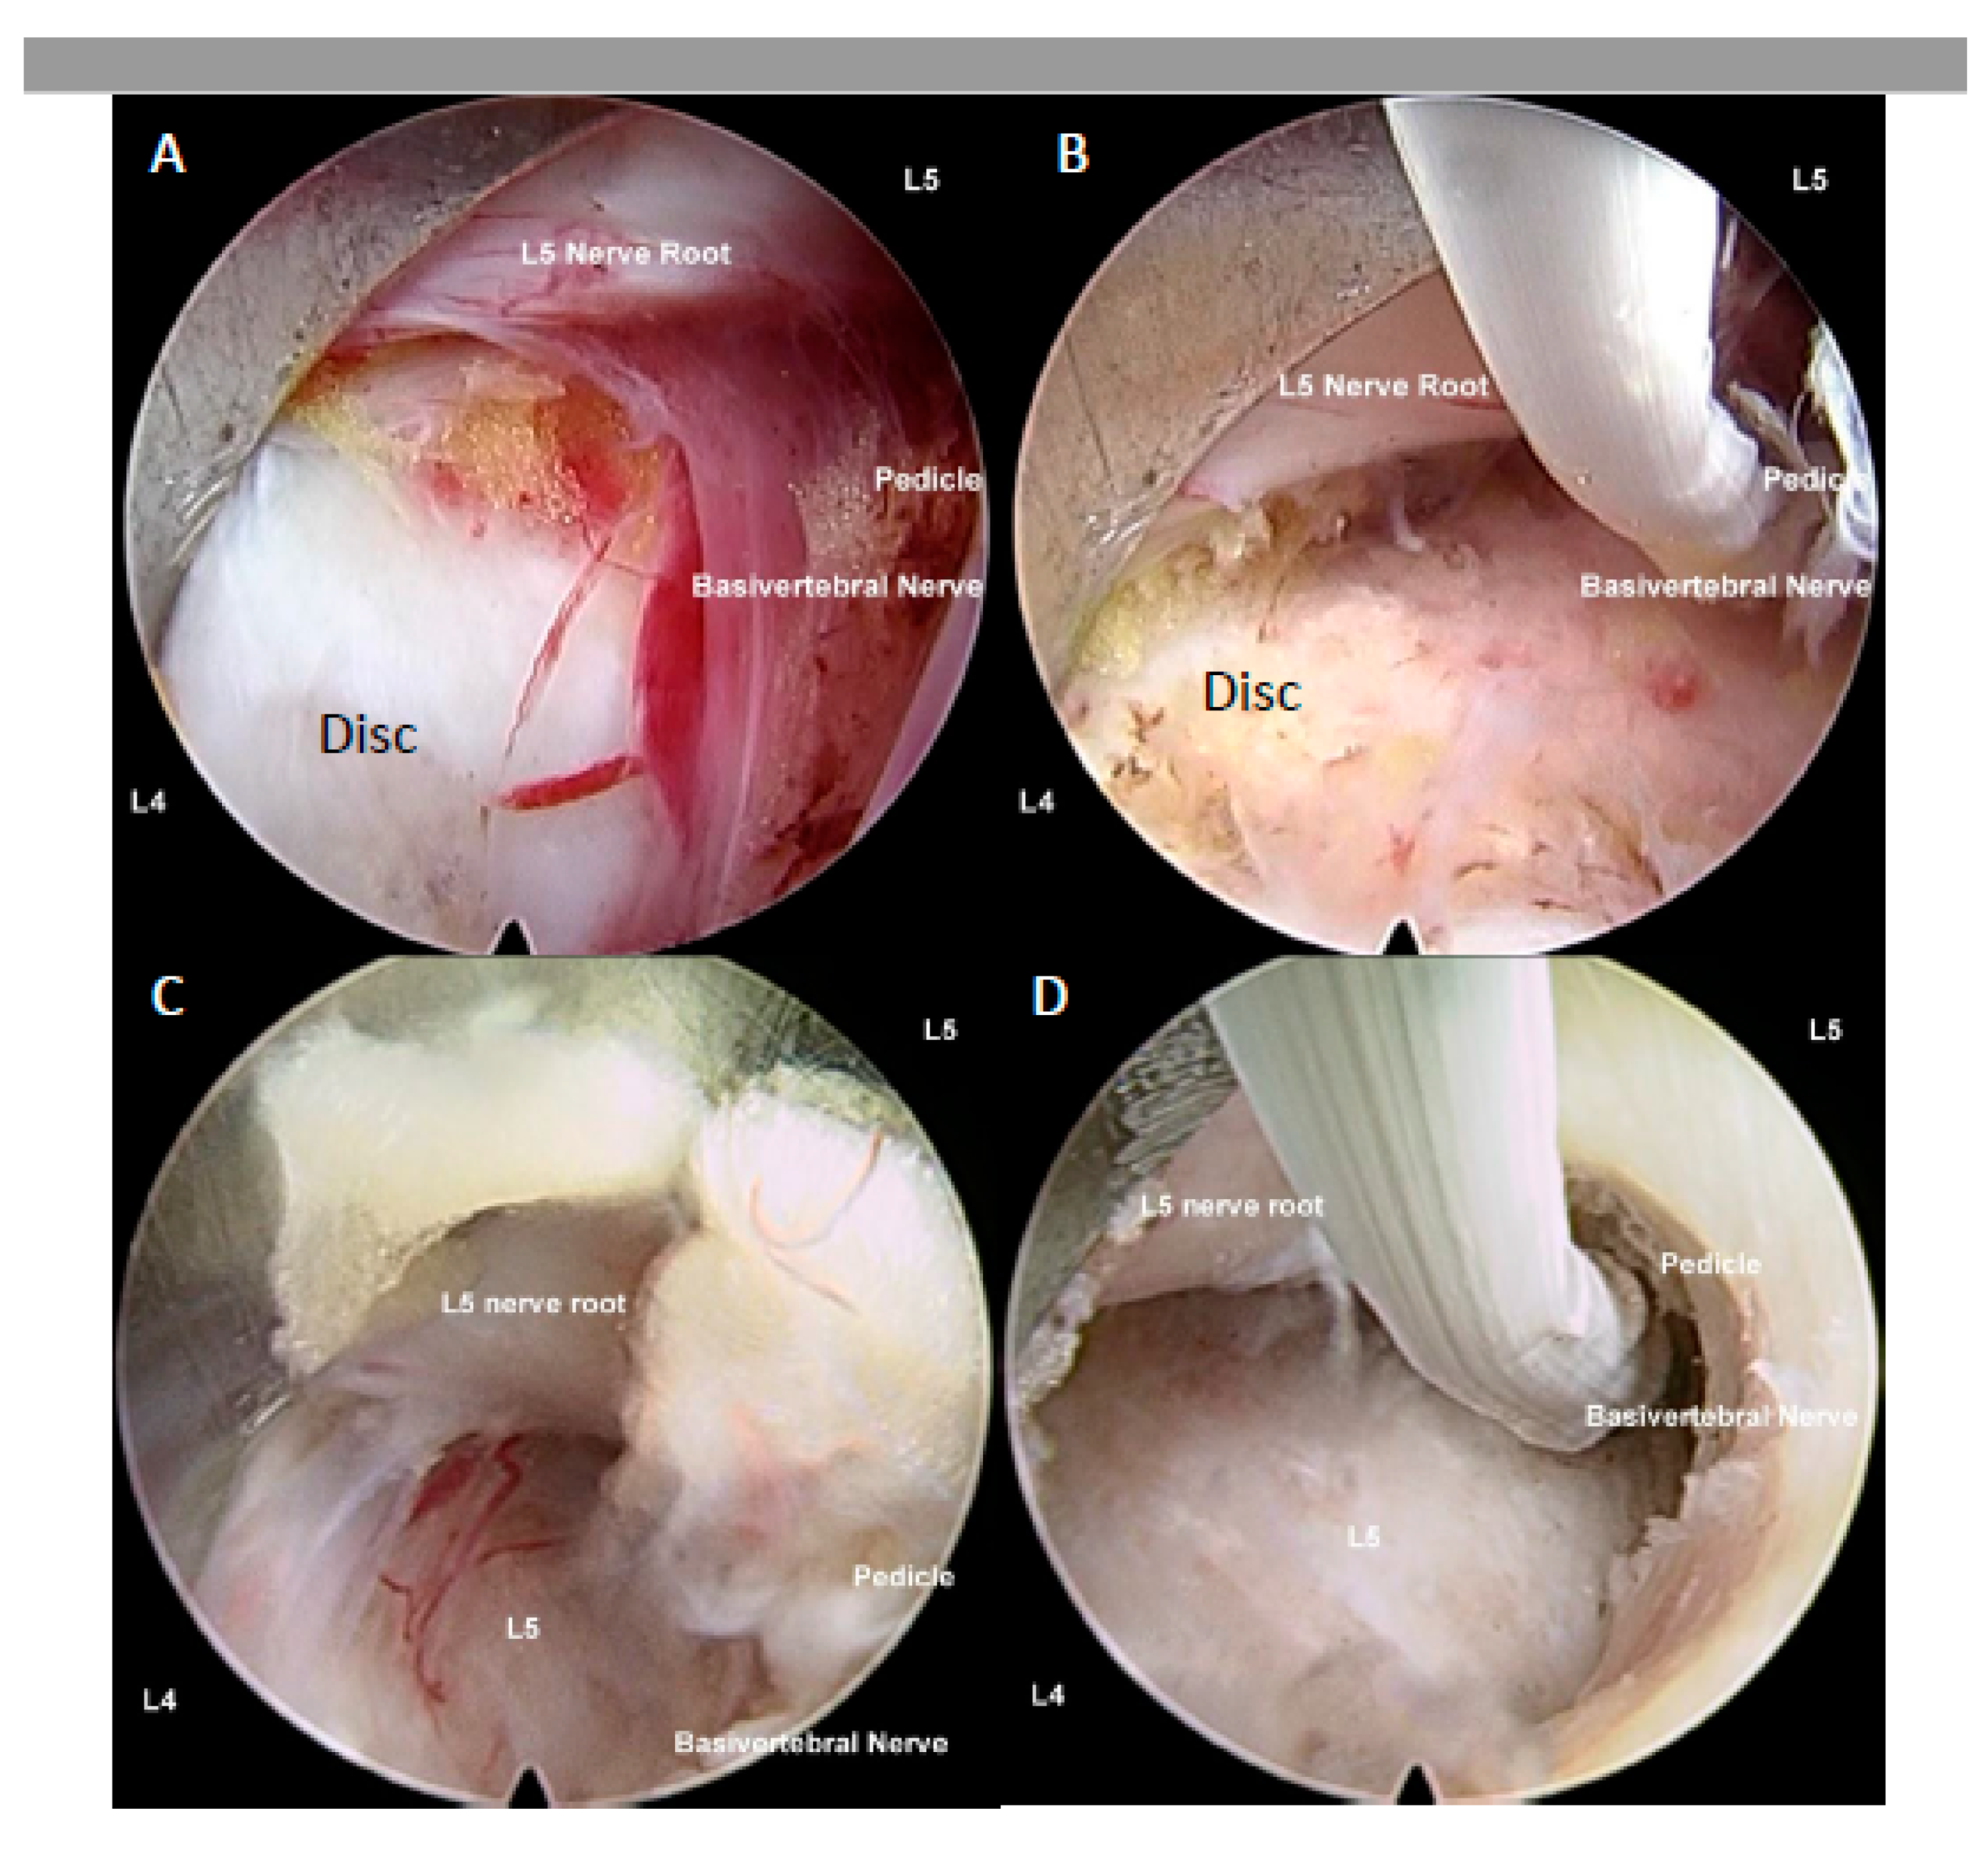

4.2. Ablation of Neuropathic Basivertebral Nerve and Sinuvertebral Nerve

4.1.1. Interlaminar Endoscopic Lumbar Approach to Disc

4.1.2. Lumbar Endoscopic Unilateral Laminotomy for Bilateral Decompression with Radiofrequency Ablation

4.1.3. Transforaminal Endoscopic Lumbar Approach for Radiofrequency Ablation